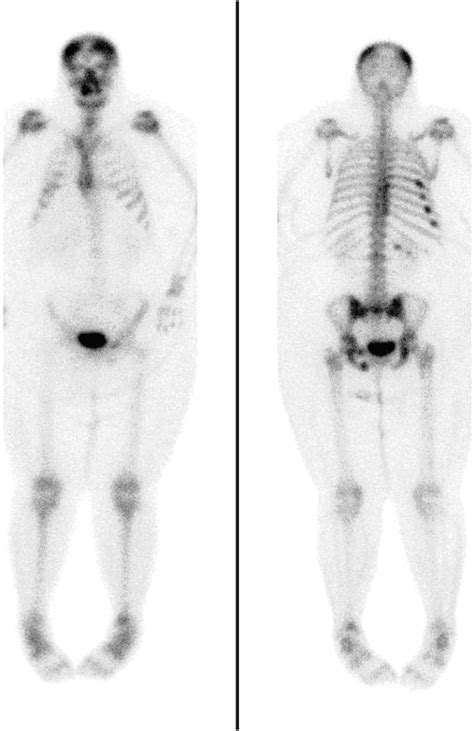

One of the most significant advancements is the use of dual-energy X-ray absorptiometry (DEXA) scans. DEXA scans use two different energy levels to differentiate between soft tissue and bone, providing more detailed and accurate images. This technology is particularly useful in cases where traditional X-rays may not provide sufficient detail.

Another advancement is the use of computed tomography (CT) scans. CT scans use a series of X-ray images taken from different angles to create detailed cross-sectional images of the body. This technology can provide more detailed images than traditional X-rays, making it easier to diagnose complex conditions.